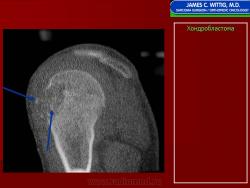

Хондробластома — это редкая доброкачественная опухоль, локализующаяся, главным образом, в эпифизе и отличающаяся своеобразным клеточным составом. Ткань новообразования представлена овальными, округлыми и веретеновидными клетками, напоминающими незрелые хондроциты (хондробласты). Зрелый гиалиновый хрящ определяется лишь в некоторых опухолях. Возраст больных варьирует. Мужчины поражаются в два раза чаше женщин. Пациенты предъявляют жалобы на боли в течение нескольких месяцев или лет, у некоторых больных определяются внутрисуставной выпот, припухлость и ограничение движений. Наиболее типичная локализация опухоли — проксимальные эпифизы плечевой и большеберцовой костей, а также дистальный эпифиз бедренной кости. У 20 % больных опухоль развивается в плоских или коротких трубчатых костях, преимущественно в пяточной и таранной. Изредка поражаются кости лицевого черепа, в том числе височная. В большинстве случаев новообразование выходит за пределы эпифиза и распространяется на метафиз. На фоне остеолиза обнаруживаются рассеянные участки обызвествления в виде пунктирных линий, а также разреженный трабекулярный рисунок. Хондробластома, как правило, не выходит за пределы кости, но изредка проникает в полость сустава. В процессе роста опухоли иногда возникает вторичная аневризматическая костная киста.

Рентгенологически хондробластома представляет собой сравнительно большой (2-4 см) очаг округлой формы, четко отграниченный от окружающей кости склеротической каймой. На фоне очага в большинстве случаев, но не обязательно определяются плотные включения, напоминающие хлопья ваты.

Рентгенологическая картина. Хондробластома выглядит как небольшой, от 3 до 6 см литический очаг, центрально или эксцентрично расположенный, с четкими контурами, занимающий около половины площади эпифизарной зоны. Хондробластома плоских костей и мелких трубчатых костей больших размеров, может сопровождаться припухлостью мягких тканей, вздутием кости и периостальной реакцией. Распространение процесса на метафизарную зону встречается часто.